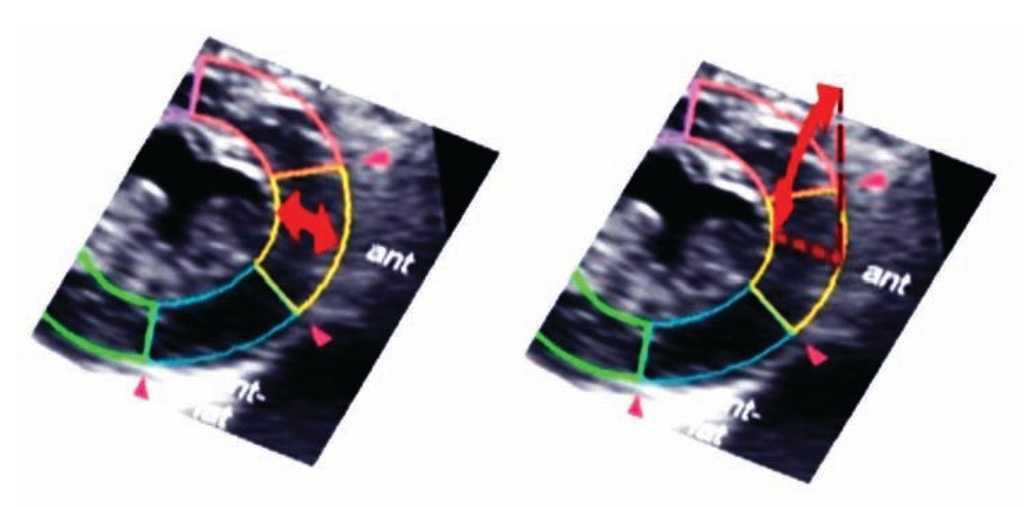

Three-Dimensional speckle tracking takes into account the motion of the cardiac wall not only in a concrete plane (radial, longitudinal, circumferential, and transversal) but also in three dimensions. The rationale for this is that from only one apical position, the entire ventricle may be analyzed; a 90 × 90° triggered full volume is obtained and the echocardiographer does not need to change to different positions to obtain different planes61 (Figure 10). That is why the three-dimensional format more closely represents reality and better accuracy than the two-dimensional format.62

Figure 10. Using a full 3D template, the software can track the complete speckle's movement through the cardiac cycle, avoiding out of plane cardiac motion.